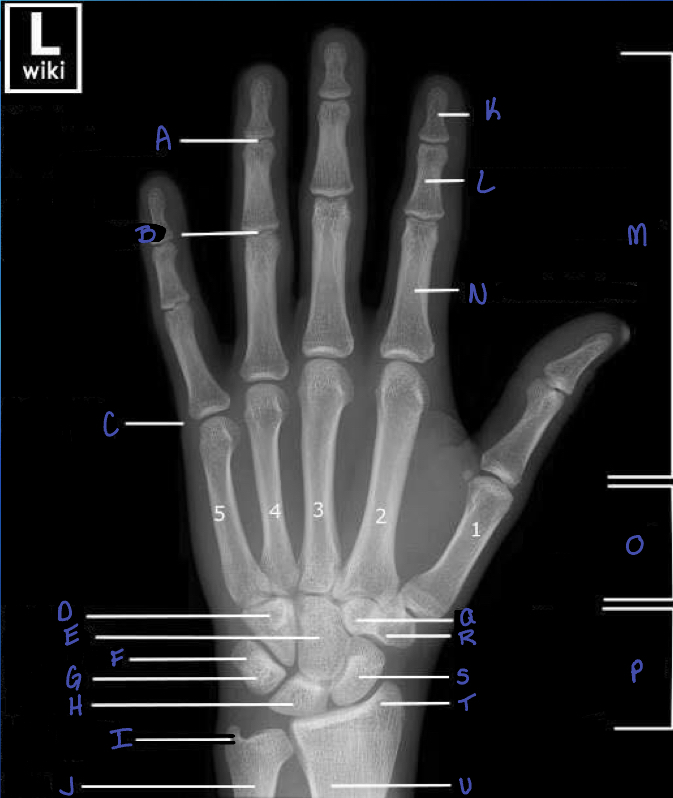

13

What is A?

distal interphalangeal joint

14

What is B?

proximal interphalangeal joint

15

What is C?

metacarpophalangeal joint

16

What is D?

hamate b

17

What is E?

capitate b

18

What is F?

triquetrium b.

19

What is G?

pisiform

20

What is H?

lunate b.

21

What is i?

ulna styloid process

22

What is J?

ulna

23

What is K?

distal phalanx

24

What is L?

middle phalanx

25

phalanges

26

proximal phalanx

27

metacarpals

What is O?

What is P?

carpals

What is Q?

trapezoid b.

30

trapezium b.

31

scaphoid b.

32

radial styloid process

33

radius